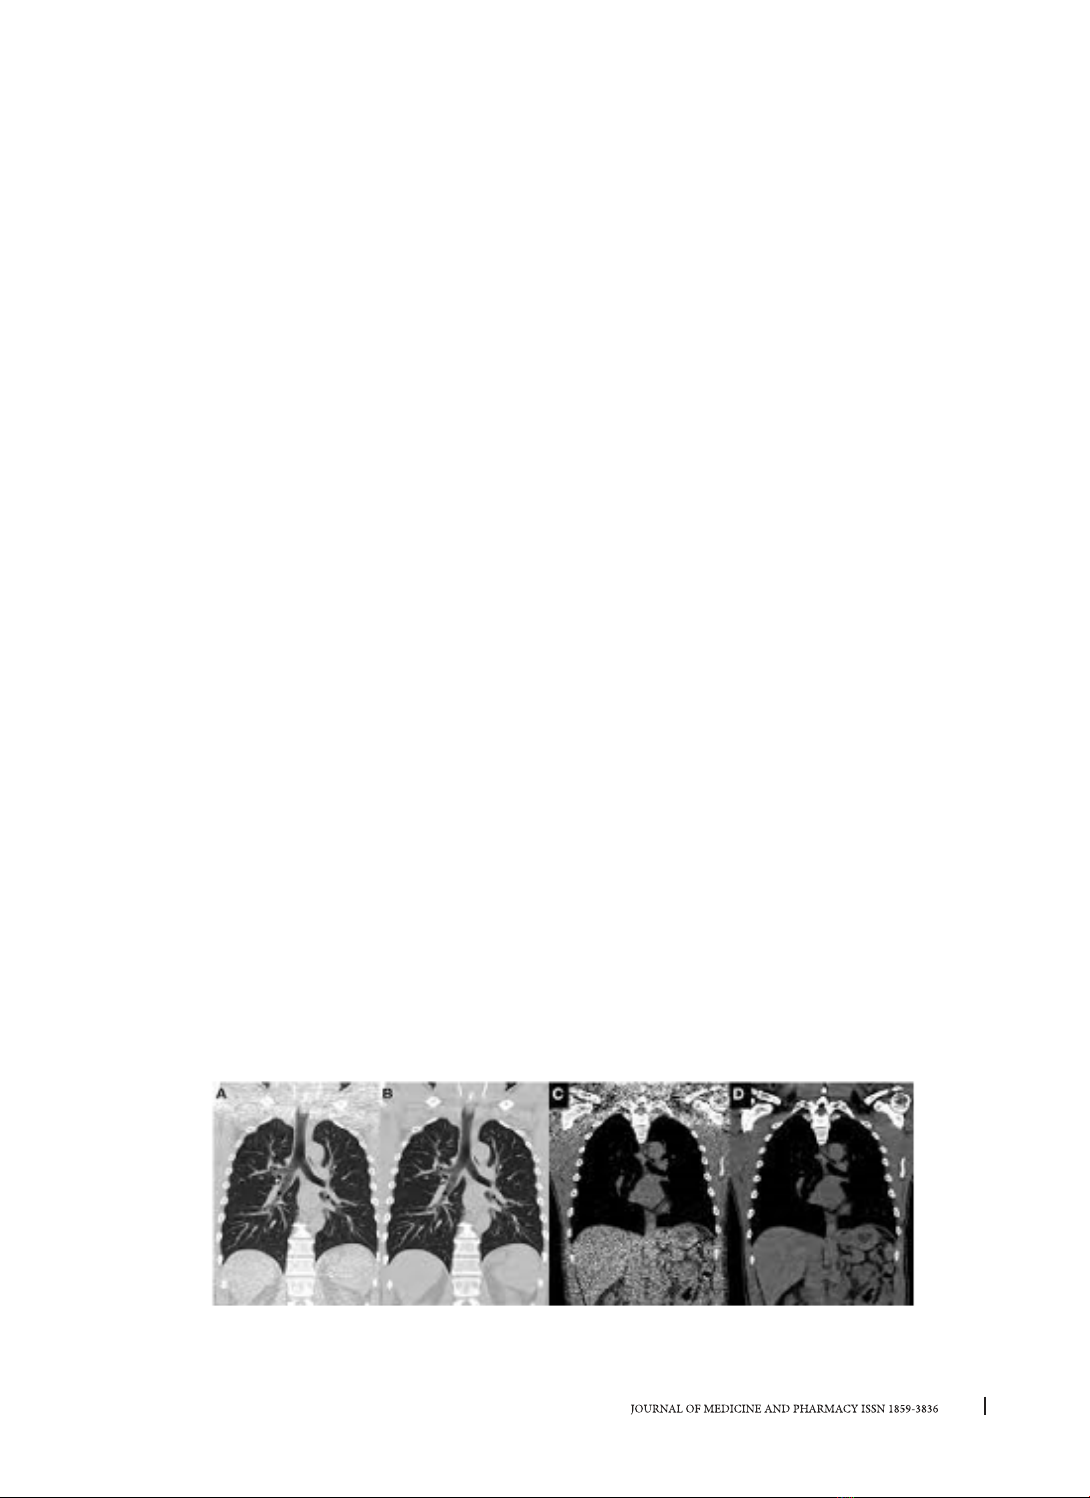

Hình 2. Hình ảnh tái tạo coronal CLVT Phổi không tiêm thuốc cản quang tĩnh mạch (1,1 mSv). Hình A, C sử

dụng thuật toán FBP và hình B, D sử dụng iDose (Philips). Sử dụng IR cải thiện chất lượng hình ảnh tốt hơn

và khắc phục được ảnh giả do chùm tia cứng ở phần vai [4].